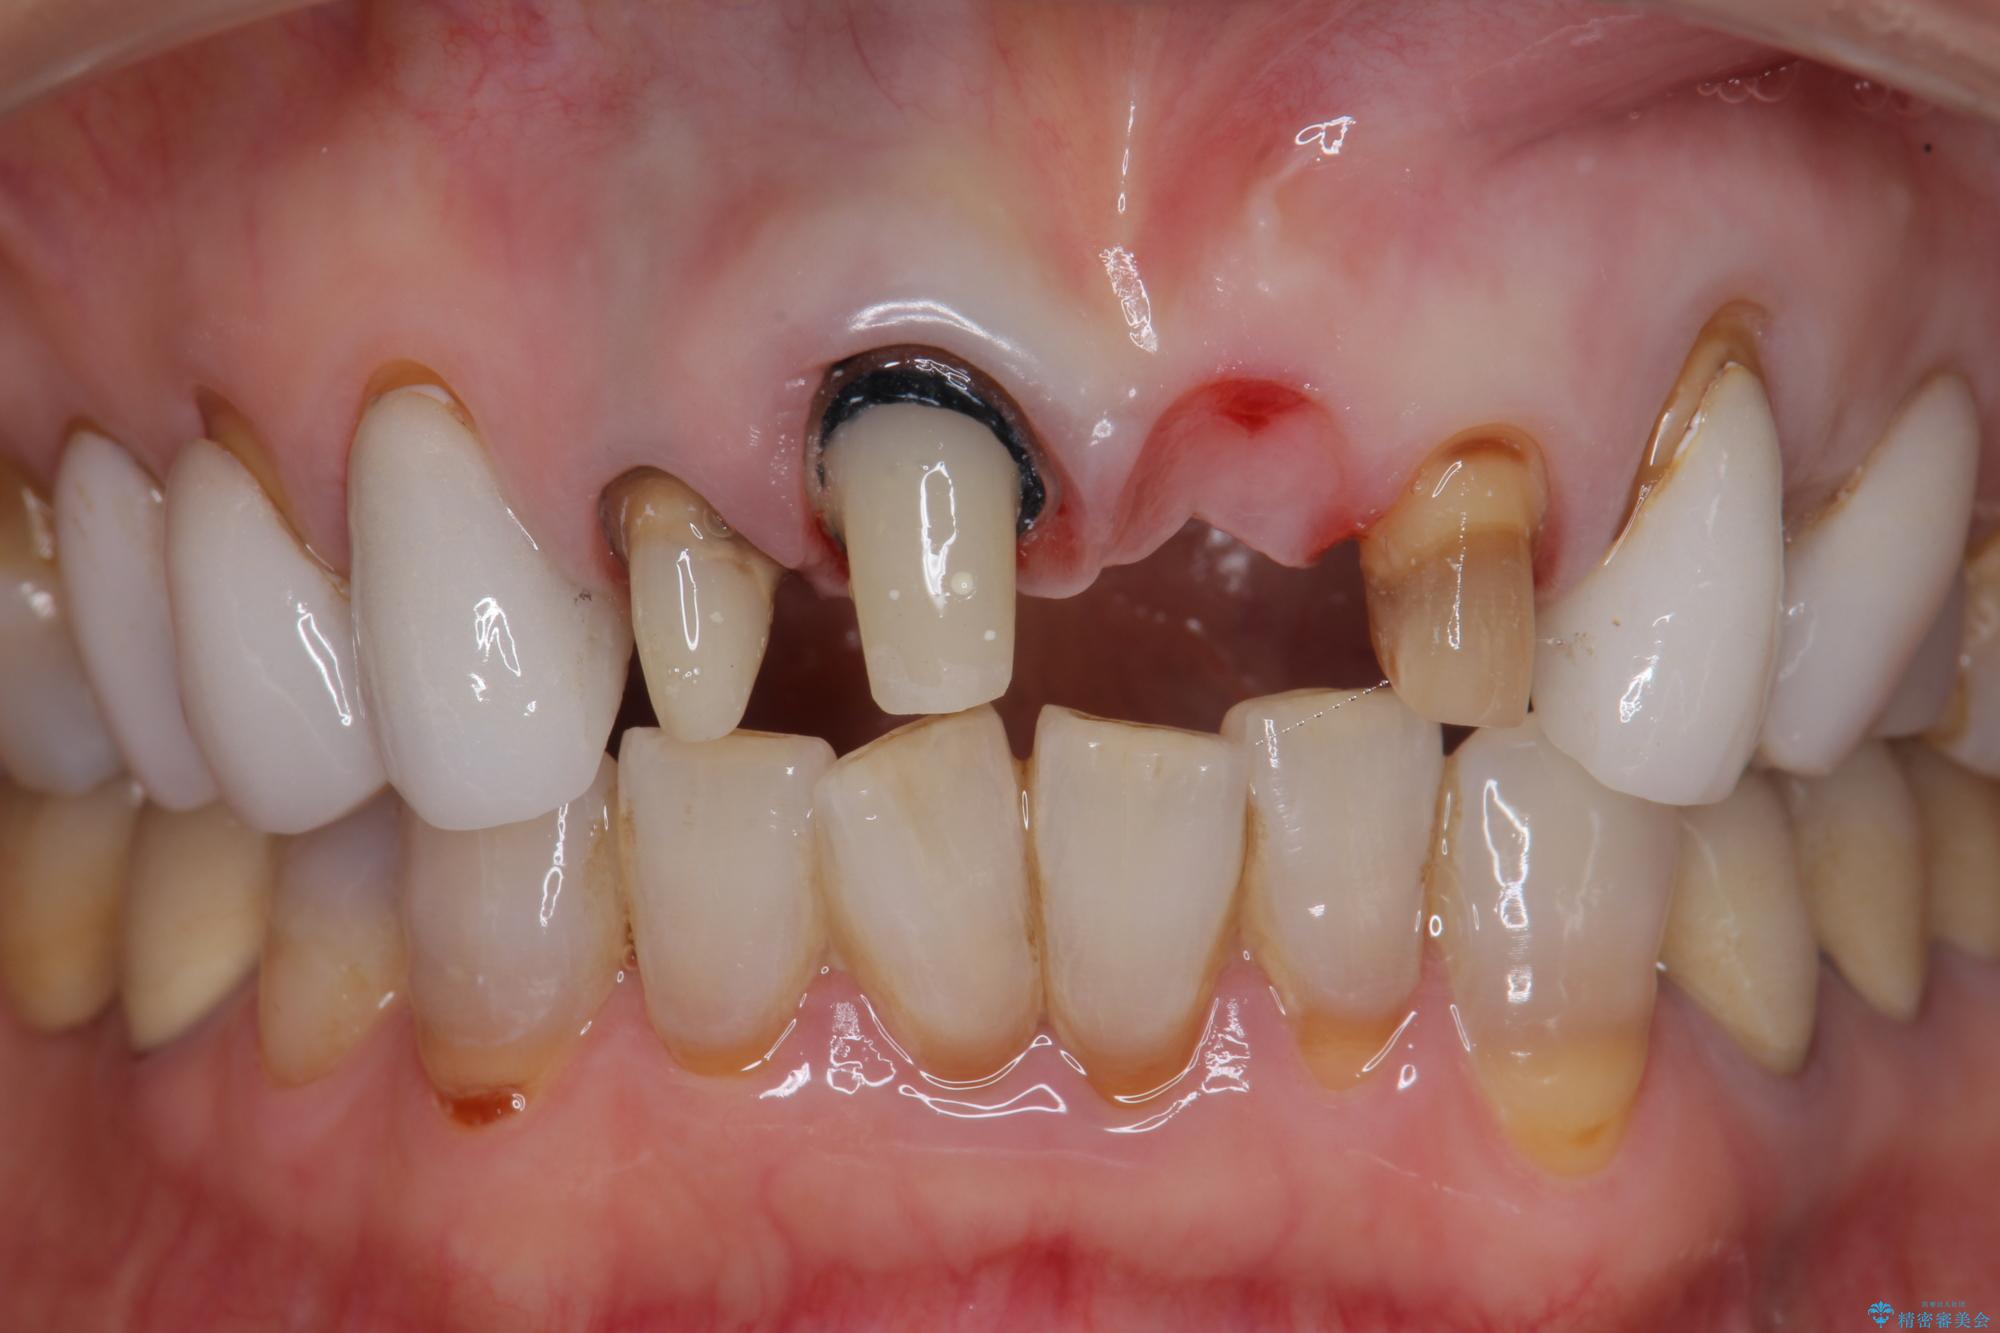

[ セラミック治療 ] 歯ぐきの際の黒ずみを改善したい

- 歯ぐきとセラミックの間の黒ずみが目立つので、きれいに治してほしい。と希望され来院されました。

歯ぐきの位置が変化しクラウン下の歯が見えるようになってしまったことで、審美障害が生じている状態です。

クラウンマージンの再設定を行うことで、黒ずんだ部分を再度覆い、審美障害を改善します。

- 52.8万円(ジルコニアクラウン×4・仮歯×4)費用は治療当時の料金となります